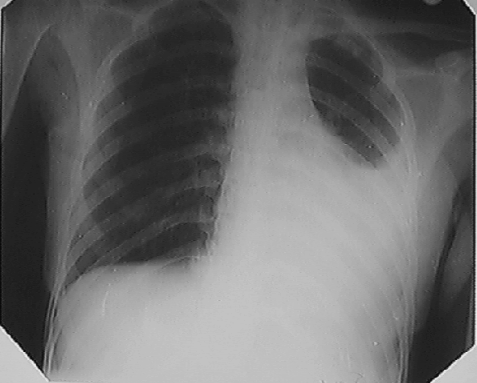

Помимо опроса и объективного осмотра, включающего перкуссию и аускультацию грудной клетки, проводят рентгенологическое исследование в двух положениях тела (в 2-х проекциях). Это основной метод обнаружения ателектазов легких.

На рентгеновских снимках выявляют следующие признаки, указывающие на спадение легочной ткани:

Однородное затемнение в области поражения. Размеры тени зависят от вида ателектаза: при долевом выявляется обширное затемнение, при сегментарном — в виде клина или треугольника, расположенного вершиной к корню легкого, дольковые ателектазы множественные и похожи на очаговую пневмонию. Дистензионный ателектаз расположен низко, около диафрагмы, имеет небольшие размеры и вид поперечных полос или темных дисков. Смещение органов: при компрессионном ателектазе смещение наблюдается в здоровую сторону, так как на стороне поражения давление больше, при обтурационном, наоборот – смещение будет в сторону ателектаза, так как на стороне поражения нарастает притягивающее отрицательное давление. Подъем купола диафрагмы – это видно по расположению печени.

Помимо всего перечисленного выше, рентгеноскопия, то есть исследование «вживую», позволяет увидеть куда смещаются органы в зависимости от фазы дыхания, кашля. Это является дополнительным признаком ателектаза, помогающим выявить тип болезни.

Во время инструментальных диагностических манипуляций важно не только установить наличие ателектаза и его точную локализацию, но и уточнить объем спавшейся ткани, чтобы определить правильную тактику лечения и объем лечебных манипуляций. На рентгенограмме для диагностики ателектаза имеет значение состояние не только ткани легких, но и корней легких, ребер, органов средостения, купола диафрагмы, плевры, плевральной полости и даже позвоночника (будет наблюдаться его сколиотическое отклонение в направлении выпуклости в сторону пораженного легкого)

На рентгенограмме для диагностики ателектаза имеет значение состояние не только ткани легких, но и корней легких, ребер, органов средостения, купола диафрагмы, плевры, плевральной полости и даже позвоночника (будет наблюдаться его сколиотическое отклонение в направлении выпуклости в сторону пораженного легкого).